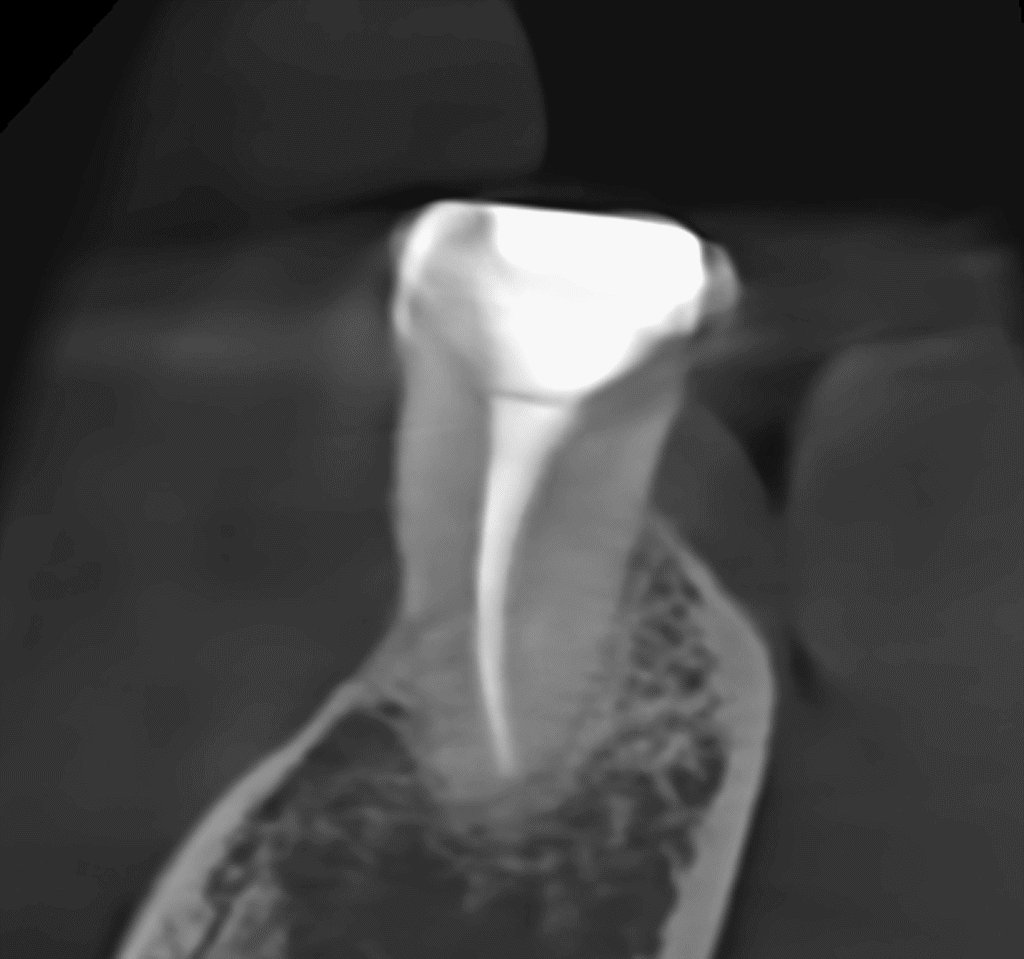

Pacjentka lat 54 trafiła do mojej kliniki skierowana z innego gabinetu celem leczenia endodontycznego zęba 46. W badaniu stwierdziłem znaczny zanik światła kanału korzeniowego. W badaniu tomograficznym stwierdziłem całkowity zanik kanału korzeniowego w strefie mezjalnej. Korzeń dystalny mimo widocznego światła kanału na CBCT, widoczne było wiele zwapnień w środkowej części kanału. Po wykonaniu dostępu endodontycznego zlokalizowałem materiał wypełniający kanał pozostawiony po poprzednim nieskutecznym leczeniu endodontycznym. Do usunięcia wykorzystałem laser 2780nm (25mJ/puls). W kolejnych etapach instrumentacji wspomaganie ultradźwiękami oczyściłem strefy mezjalną i dystalną. Instrumentacja themo-

mechaniczna polegała na zastosowaniu protokołu ciągłej chelacji wraz z użyciem lasera

2780nm z końcówką płaską (50mJ/puls) celem udrożnienia przestrzeni endodontycznych. Po wstępnym uzyskaniu drożności zastosowałem instrumentację maszynową wspomagająco celem udrożnienia przestrzeni. Finalnie obturacja z zastosowaniem ćwieków gutaperkowych kalibrowanych na WL i uszczelniacza na bazie krzemianów wapnia. W przeciwieństwie do tradycyjnych uszczelniaczy, nie wymaga mieszania, co eliminuje błędy w proporcjach i zapewnia powtarzalną konsystencję. Jest materiałem wysoce biokompatybilnym i bioaktywnym. Finalnie zamknięto ząb odbudową kompozytową tymczasową i skierowano na dalsze leczenie protetyczne do gabinetu kierującego pacjenta.